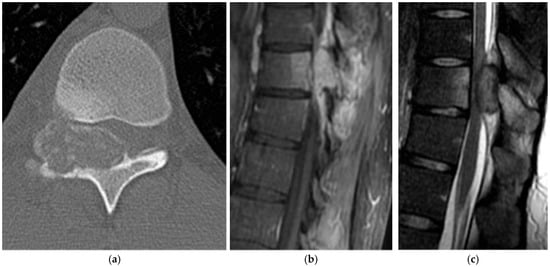

2.1.3. Osteoblastoma

2.1.4. Osteosarcoma